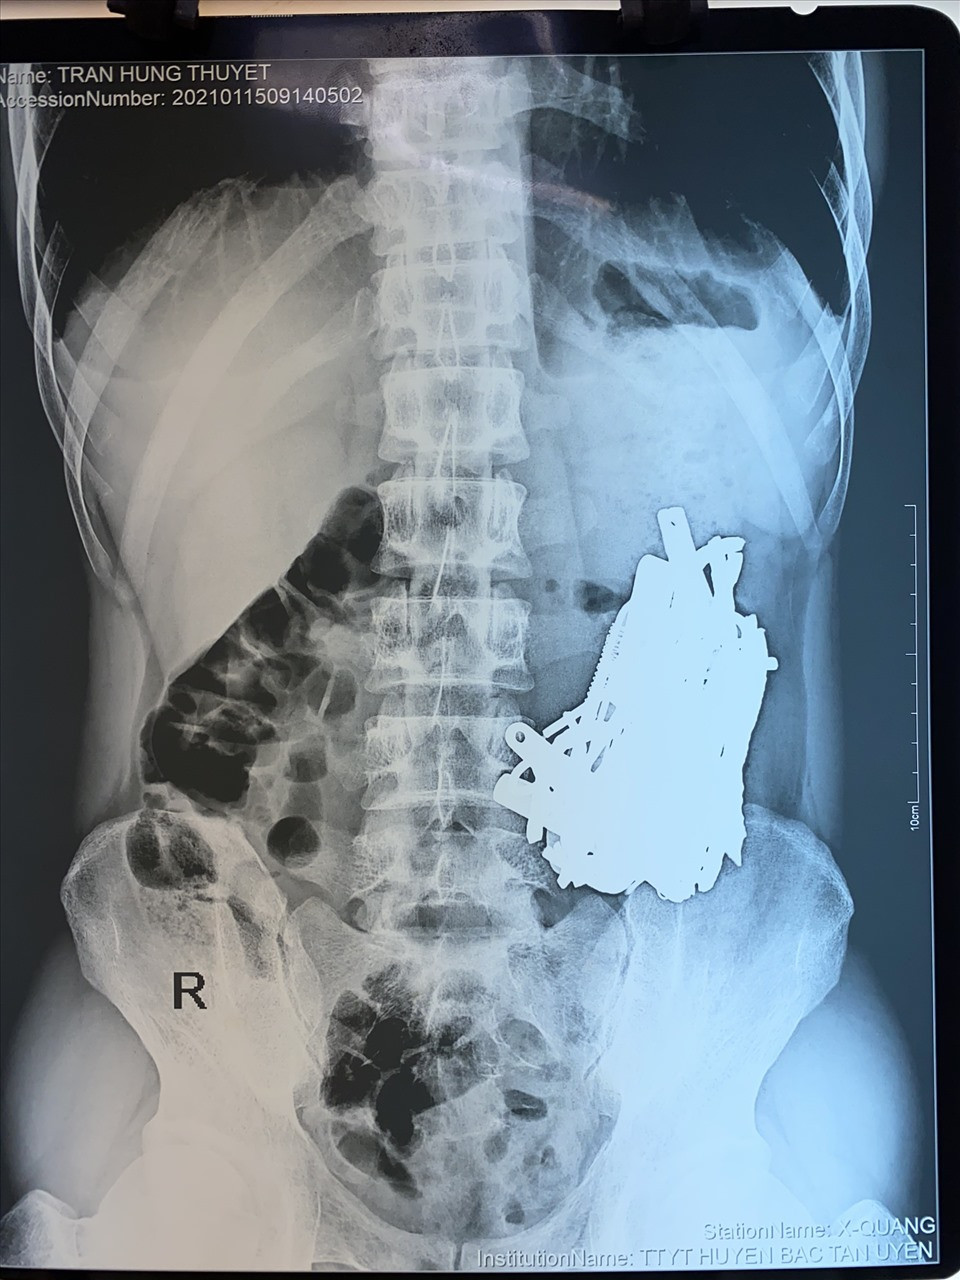

| X-quang cho thấy dị vật của bệnh nhân. Ảnh: Bệnh viện cung cấp. |

Hình ảnh chụp X-quang cho thấy có một nhóm dị vật lạ, số lượng lớn đó là đá sỏi, nắp chai và đồng xu trong dạ dày của bệnh nhân.